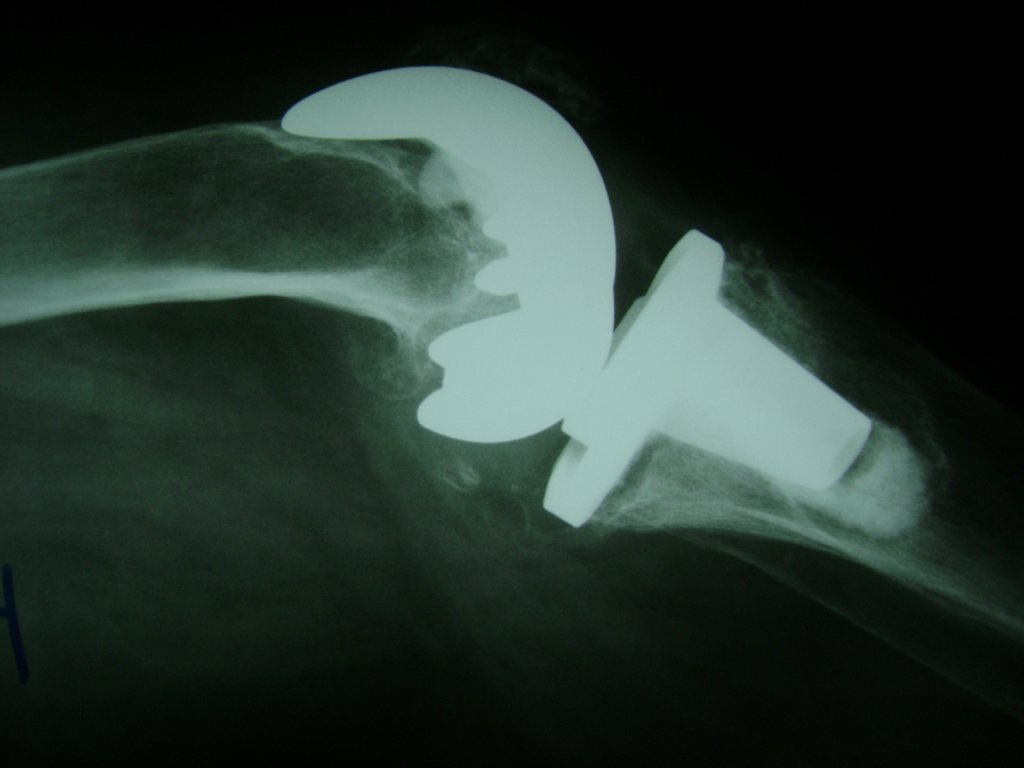

Cirugías de Calcaneo - Rodilla